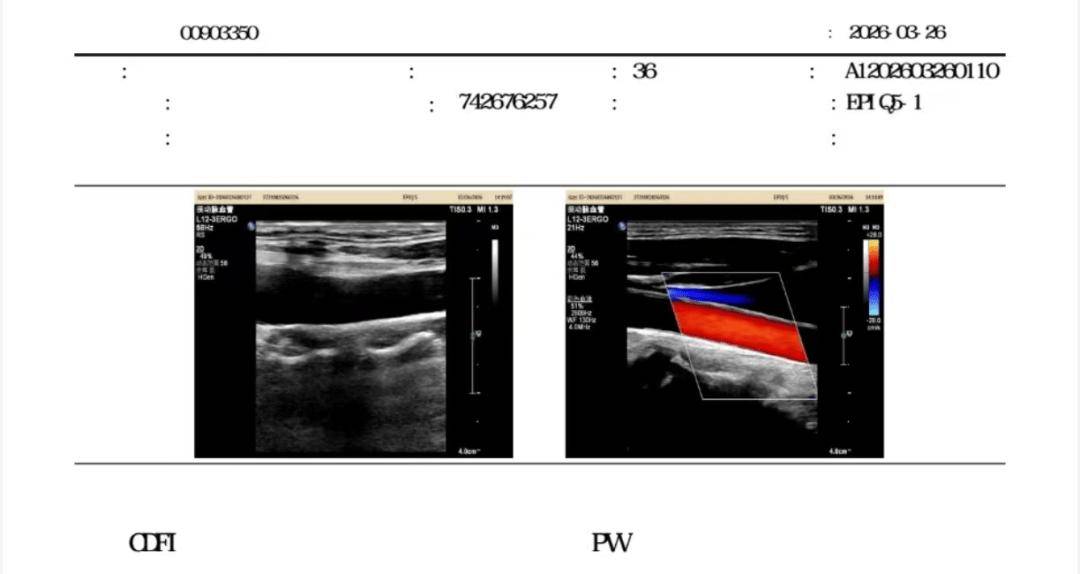

复查时:

3个月后复查:斑块完全消失!

坚持干预 3 个月后,体重仅仅下降1.5kg,但颈动脉B超显示7mm斑块彻底消失,查血显示丙氨酸氨基转移酶、天门冬氨酸转移酶、总胆固醇水平降至正常。